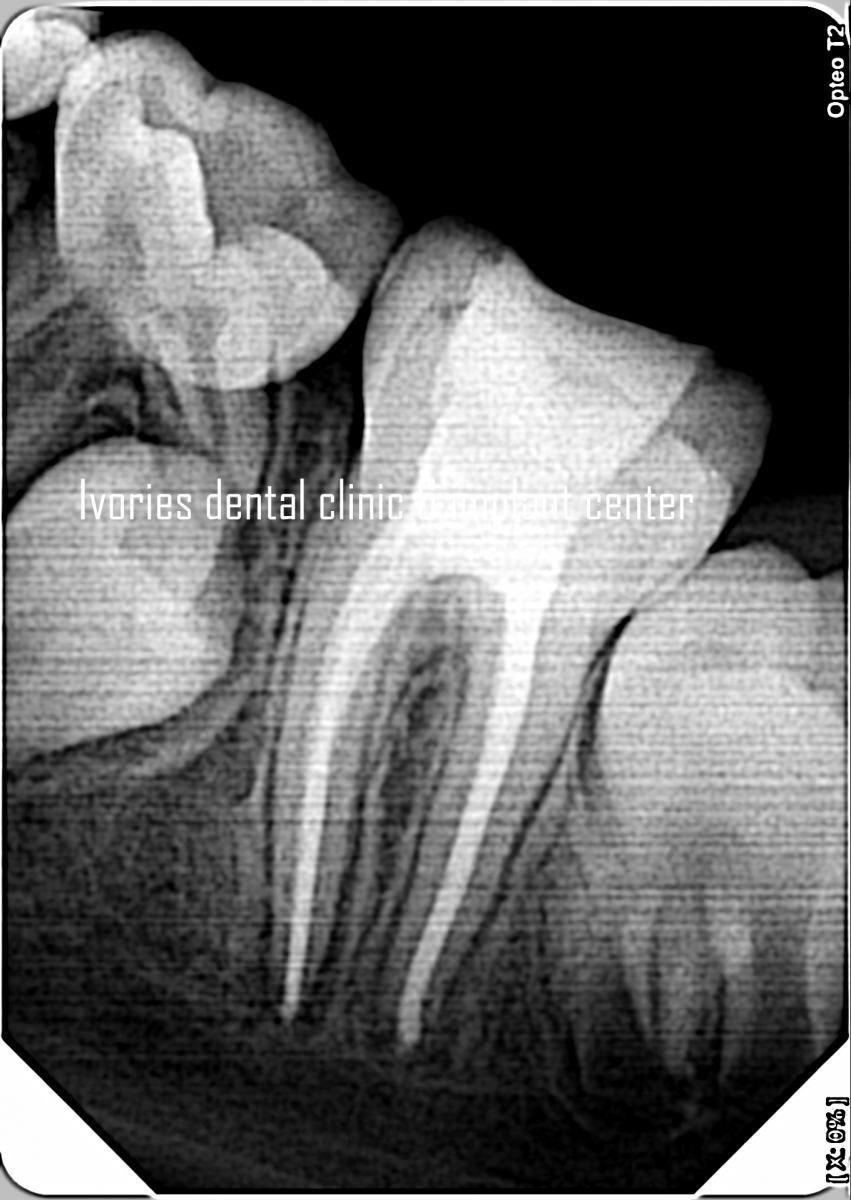

- 3D overview of anatomy of pulp canals

- Tips & tricks to locate the canals & avoid perforations!

- Complications During RCT and management of Failures after RCT!